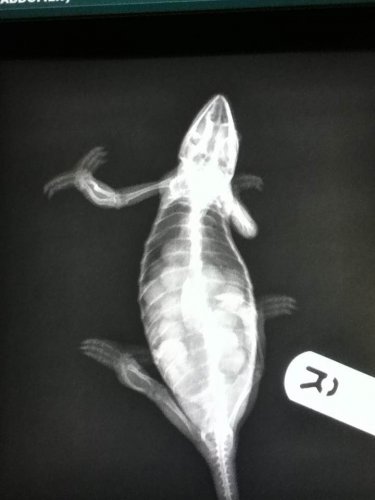

here is her xray! vets went well. she is very healthy, and has around 22 eggs (according to the vet). I attached a picture.

Attachments

• xray.jpg

xray.jpg

51.1 KB · Views: 215